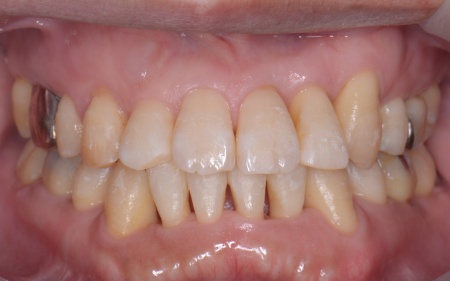

①抜歯をしてから歯並びを整える「抜歯矯正」 今回のケースでは、左上下の奥歯各1本(第3大臼歯)、右下の奥歯1本(第3大臼歯)、左上下と右下の奥歯各1本(第1小臼歯)の計6本の抜歯が必要です。 また、奥歯の噛み合わせは正常だったことから、それを維持しながら歯並びを整えるために以下の方法を採用します。 ②矯正治療後、歯周病を発症している左下奥歯(第1大臼歯)を温存するために、失われた骨や歯茎を再生する「歯周再生療法」を行う まずは歯の移動スペースを確保するために、計6本の歯を抜きます。 矯正治療終了後、歯の後戻りを防ぐため、上下前歯の裏側にワイヤーを接着して固定させる「フィックスリテーナー」を装着しています。 その後、左下奥歯に歯周再生療法を行って歯周病が改善したことを確認し、治療を終了しました。 |